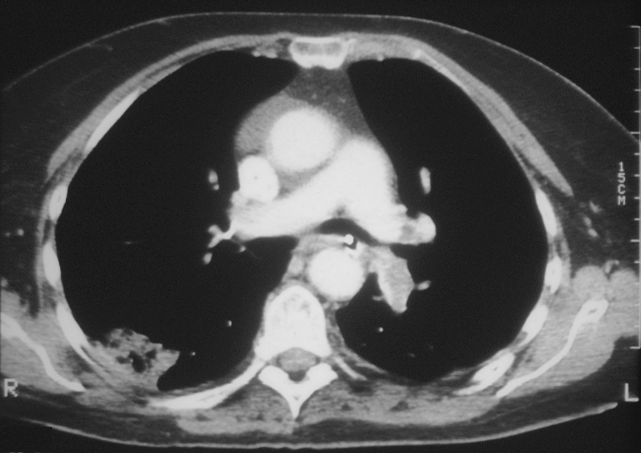

Cóagulos observados por Tomografía Computarizada